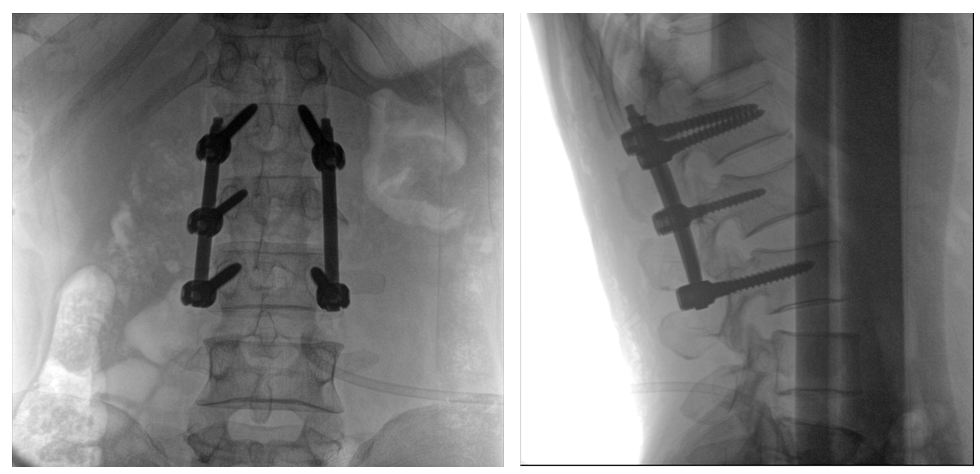

普愛(ài)醫(yī)療PLX119C大平板一體式C形臂采用30CM×30CM的平板探測(cè)器,在脊柱和長(zhǎng)骨骨折等骨科手術(shù)治療中,獲取更大視野、更清晰的骨折部位圖像,能夠有助于醫(yī)生在術(shù)中及時(shí)了解和評(píng)估骨折部位的對(duì)位、對(duì)線情況,且能進(jìn)行長(zhǎng)度和角度測(cè)量,為進(jìn)一步提高手術(shù)質(zhì)量提供強(qiáng)有力的支持。